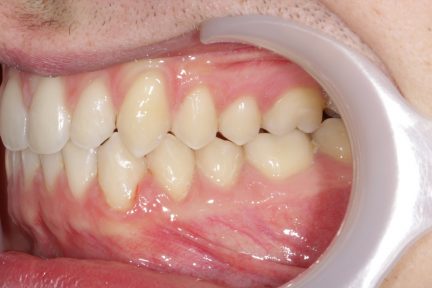

Résultats obtenus

- Relation de classe I obtenue

- Guidage fonctionnel des canines des deux côtés

- Articulé antérieur corrigé

- Forme de l'arcade améliorée

- La ligne de sourire esthétique a été obtenue

- Des arcades harmoniques ont été réalisées

État final